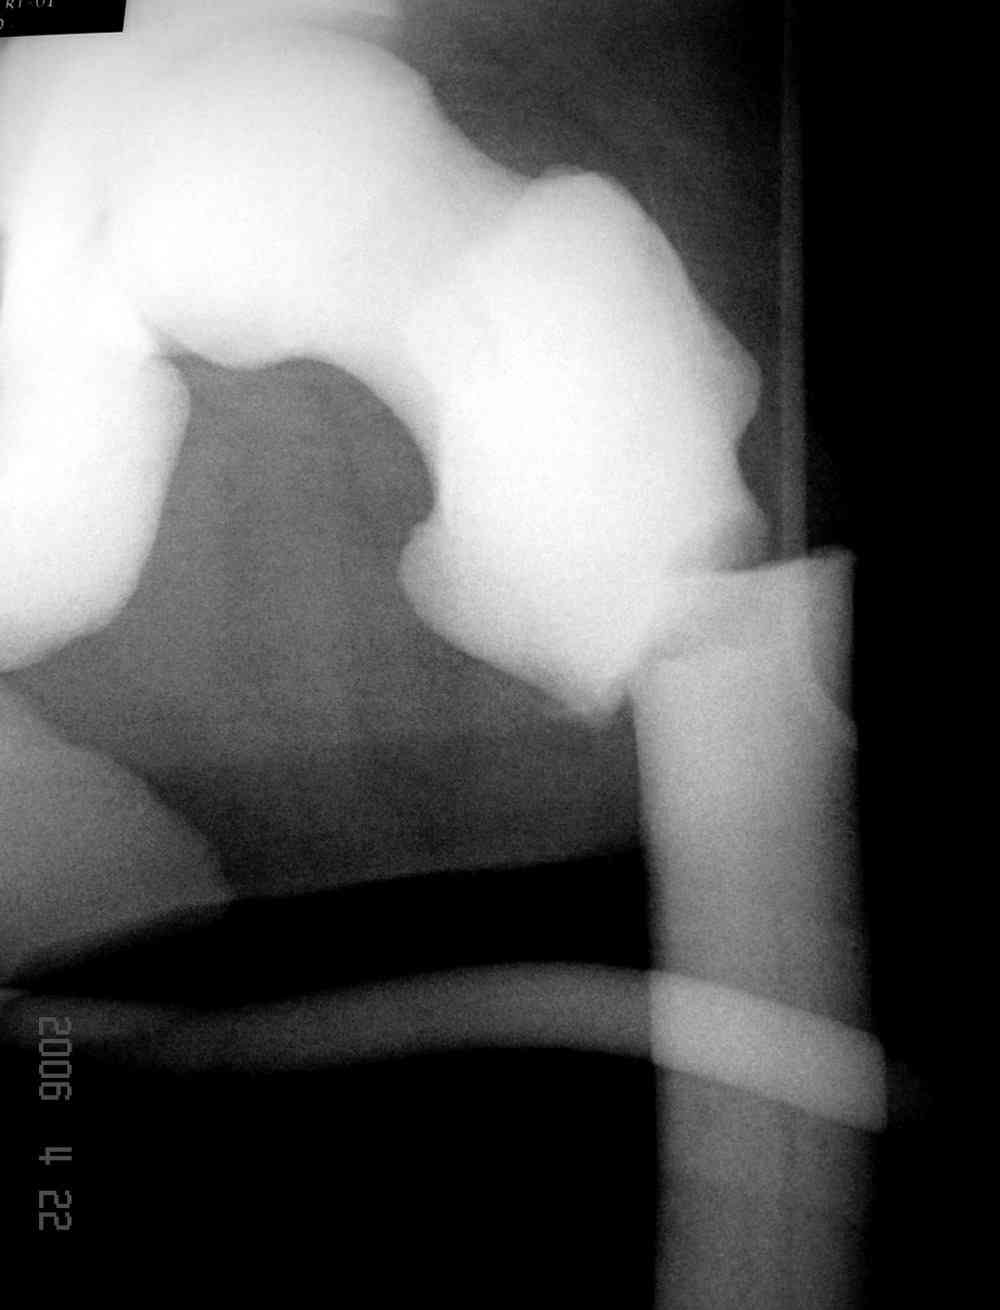

Здесь у меня дополнительные снимки с большим разрешением и в разных режимах, а то те дигитал снимки совсем очень блеклые, может, эти изображени изменят выбор тактики

После неудачной попытки скелетного вытяжения в первом мед.учреждении, после осмотра снимков и изучения истории, поставили диагноз “Остеопетроз” или мраморная болезнь, редкая наследственная костная паталогия, где имеется нарушение формации остеокластов.

Не вызывает ли подозрение, что отсутствует медуллярный канал, как просверлить канал?